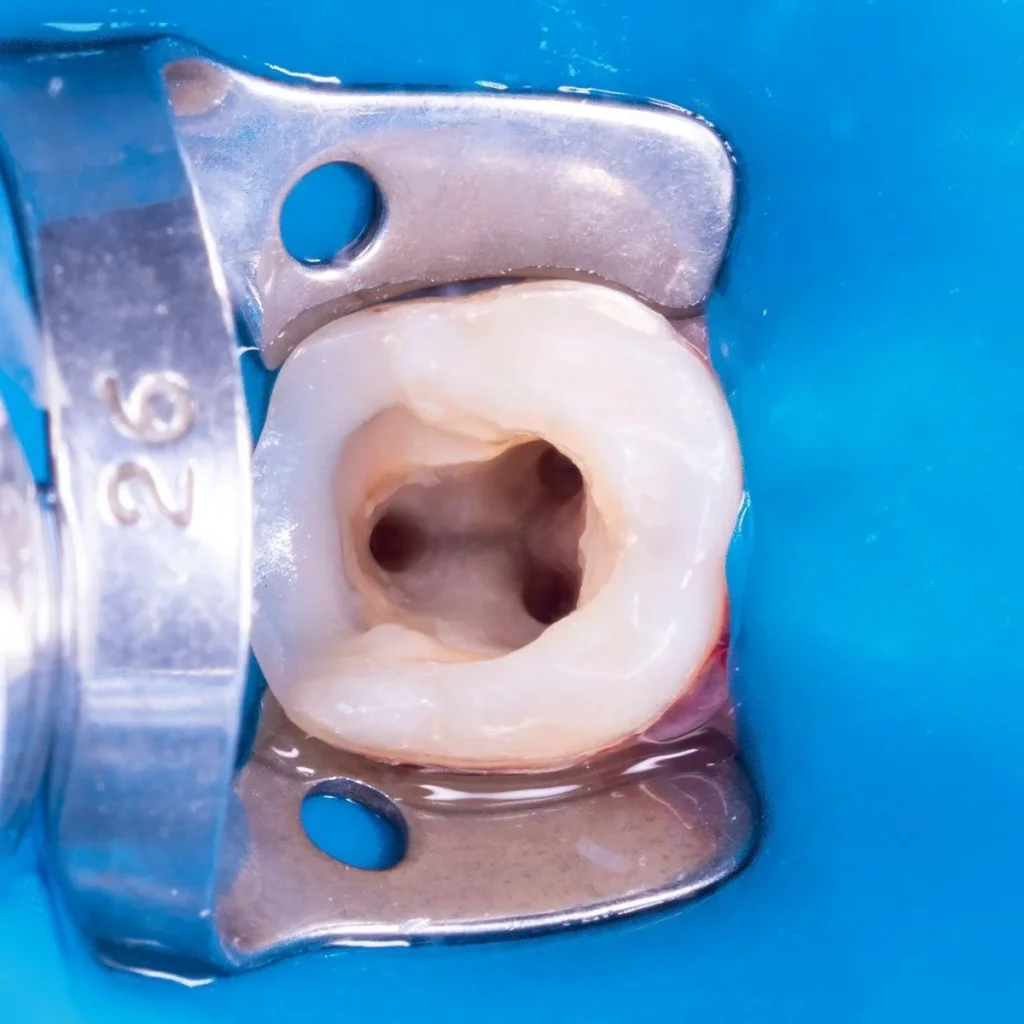

At our clinic, we believe that prevention is the cornerstone of lifelong oral health. Through regular check-ups, professional oral hygiene, and personalized care, we help our patients maintain healthy teeth and gums while avoiding future complications. When treatment is needed, we offer comprehensive services – from the early management of caries and aesthetic dental restorations to advanced procedures like the treatment of pulpitis and periodontitis. For complex cases, we perform dental treatments under a microscope to ensure precision and long-lasting results. If tooth removal becomes necessary, we ensure it is done gently and safely, with a focus on your comfort and recovery. We also offer cosmetic enhancements such as teeth whitening to help you achieve a bright, confident smile. Whether you’re here for prevention, treatment, or aesthetic care, our goal is to restore and protect your smile with the highest standard of dentistry.